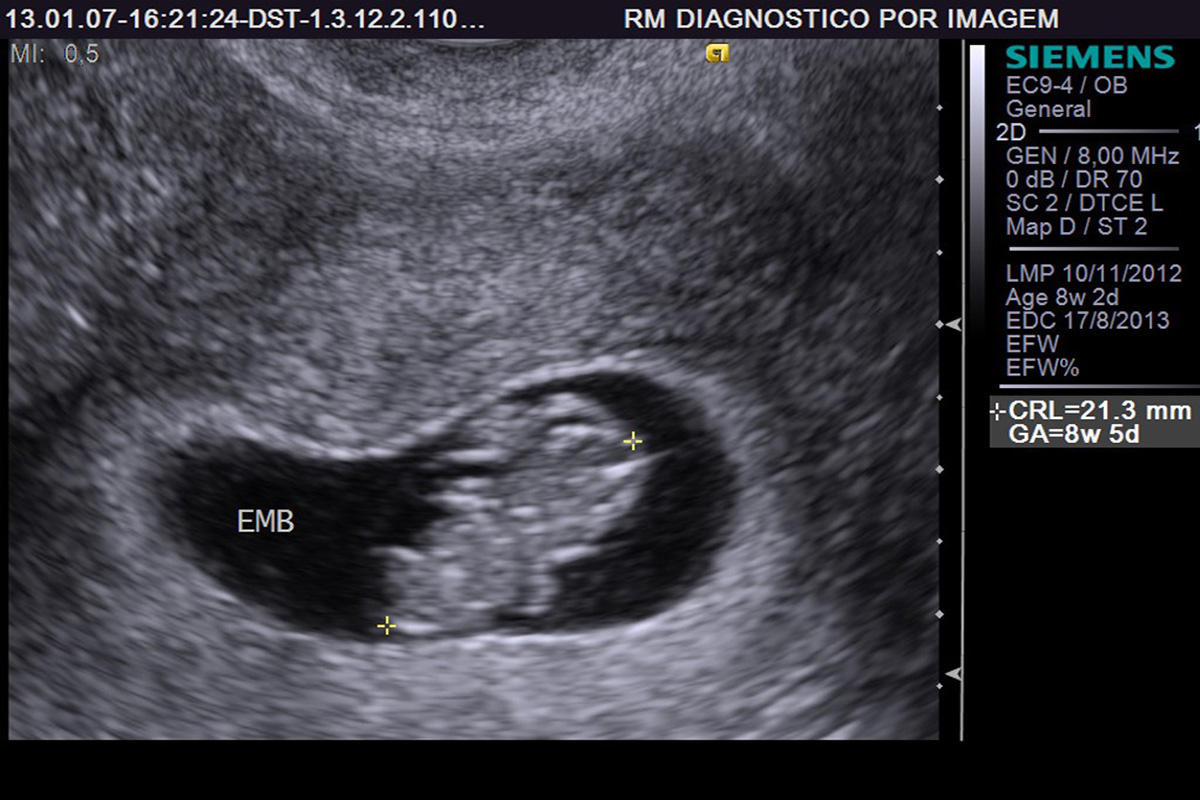

US Obstétrica Transvaginal no Primeiro Trimestre Clínica RM

Ultrassom Morfológico de Primeiro Trimestre Origem Med